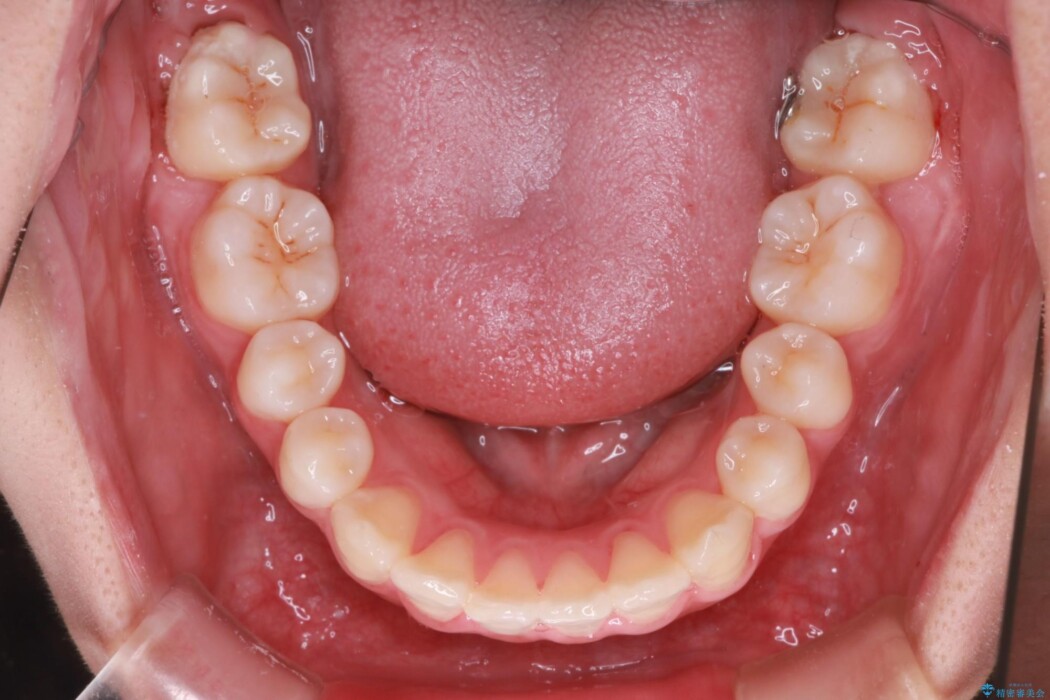

治療前

• 抜歯矯正で口元スッキリ きれいな笑顔に 治療前画像

前歯の叢生(デコボコ)と口元の突出感を主訴にご来院されました。

前歯のデコボコと突出を改善するための歯のスペースがなかったため、上顎両側小臼歯を抜歯してのワイヤー矯正をご提案しました。